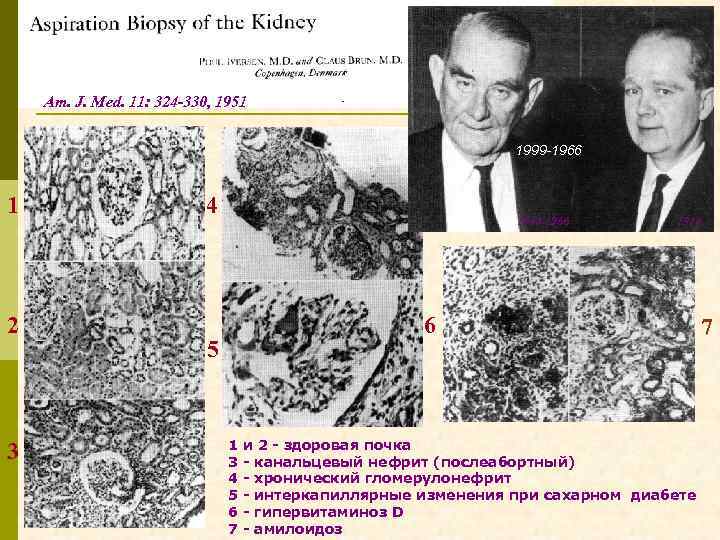

ИСТОРИЧЕСКИЕ АСПЕКТЫ ДИАГНОСТИЧЕСКОЙ НЕФРОБИОПСИИ p Nills Alwall в 1943 – 44 г. выполнил 13 биопсий p 1950 – Perez-Ara, кубинский военный врач, сообщил о выполнении биопсии почки p Claus Brun выполнил первую биопсию 19 мая 1949 г. p 1951 – классическая статья Iversen и Brun p 1957 – электронномикроскопический анализ p 1959 – иммуногистологическое исследование p 1958 – Robert Kark и Сlaus Brun опубликовали материалы, содержащие по 500 нефробиопсий p 1960 – в мире выполнено 5000 нефробиопсий p 1963 – «диагностическая нефробиопсия стала рутинным нефрологическим методом»

Am. J. Med. 11: 324 -330, 1951 1999 -1966 1 2 3 4 1884 -1966 1914 6 5 1 3 4 5 6 7 и 2 - здоровая почка - канальцевый нефрит (послеабортный) - хронический гломерулонефрит - интеркапиллярные изменения при сахарном диабете - гипервитаминоз D - амилоидоз 7

ИСТОРИЧЕСКИЕ АСПЕКТЫ ДИАГНОСТИЧЕСКОЙ НЕФРОБИОПСИИ p Nills Alwall в 1943 – 44 г. выполнил 13 биопсий p 1950 – Perez-Ara, кубинский военный врач, сообщил о выполнении биопсии почки p Claus Brun выполнил первую биопсию 19 мая 1949 г. p 1951 – классическая статья Iversen и Brun p 1957 – электронномикроскопический анализ p 1959 – иммуногистологическое исследование p 1958 – Robert Kark и Сlaus Brun опубликовали материалы, содержащие по 500 нефробиопсий p 1960 – в мире выполнено 5000 нефробиопсий p 1963 – «диагностическая нефробиопсия стала рутинным нефрологическим методом»